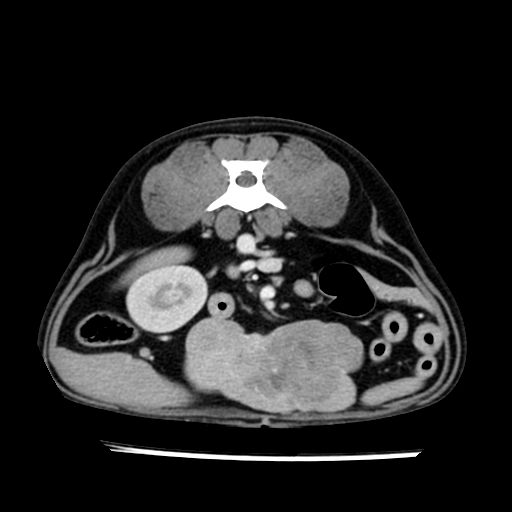

prescritto esame TAC

sequenza immagini limitata al fegato reni e surreni

le immagini ecografiche rispetto alla tac datano circa 7 mesi prima ,le surrenali sono normali nonostante il test acth sia risultato positivo .all’esame TAC dopo diversi mesi risultano aumentate armonicamente nel volume e si individua un forte sospetto di adenoma ipofisario .

sospetto adenoma ipofisario vs. meno probabilmente meningioma della base; intertiziopatia polmonare; lesione espansiva epatica, verosimilmente del lobo laterale sinistro, di sospetta natura neoplastica; lesioni spleniche di natura da definire; iperplasia/ipertrofia delle ghiandole surrenali, bilateralmente; vertebra di transizione del rachide toracico; tenosinovite cronica del muscolo bicipite brachiale di destra.

la tac dopo 7 mesi permette misure tridimensionali 5,2 x 9,2 x 4,5 cm (forma piu’ allungata )